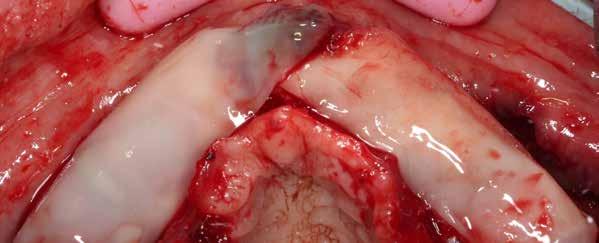

Az 50 éves nőpáciens az alsó és felső állcsont területén egyaránt panaszt (fájdalom, ráharapási érzékenység) okozó, harmadfokban mozgatható fogak miatt jelentkezett rendelőnkben. Az általános anamnézisben említést érdemlő betegség, műtét nem szerepelt. Az elvégzett klinikai és radiológiai vizsgálatok (1–2. ábra) alapján fogai reménytelen parodontális státusúnak bizonyultak, hosszú távon sem megtartásuk, sem protetikai célú felhasználásuk nem volt lehetséges. A parodontális prognózis a fogak eltávolításának abszolút indikációját jelentette. Ezáltal mindkét állcsontban teljes foghiány kialakulásával kellett számolnunk. A protetikai szemléletű, „visszafelé” tervezés elveit követtük a hosszú távú funkcionális, esztétikai siker és szöveti stabilitás elérése érdekében: mindkét állcsontban overdenture típusú fogpótlás készítése mellett döntöttünk. A megfelelő implant-protetikai rehabilitáció alapja az implantátumok megfelelő pozicionálása. A korábbi parodontális kórfolyamat következtében a processus alveolarisokat érintő eredendő csontdeficittel kellett számolnunk, amelyet tovább súlyosbíthatott volna a hagyományos extrakciós technikát követő involúciós atrófia. Ezért a páciens kivizsgálása és megfelelő előkészítése után a fog eltávolításával egy időben PRF

A fogak eltávolítása és az alveoláris csont megőrzésének és regenerációjának segítése céljából elvégzett augmentáció altatásban történt. Óvatos, atraumatikus extrakciót követően eltávolítottuk a parodontális és periapikális gyulladásos folyamatok eredményeként jelen lévő sarjszövetet. A bukkális csontfal hiánya és a tervezett vertikális augmentáció miatt indokolt membrántechnika megfelelő kivitelezése céljából a felső állcsonton mukoperioszteális lebenyt képeztünk (3–4. ábra). Az alveolus prezervációt Sticky Tooth, PRF és titánerősítésű teflon (PTFE-Ti) membránok segítségével végeztük el, a J. Choukroun által megadott vérvételi és centrifugálási protokoll (28) elveinek betartásával: kizárólag Process for PRF Duo Quattro System eszközöket, centrifugát, vérvételi egységet és csöveket, a membránok előállításához PRF Boxot használtunk. Az A-PRF és S-PRF csöveket a PomPac eljárásnak megfelelően 4 Celsius-fokra előhűtöttük. Az eltávolított fogak makroszkópos tisztítását és darabolását nagy fordulattal (300 000 RPM) fogászati turbinába helyezett gyémántfúróval végeztük, majd Tooth Transformer™ berendezéssel, annak gyári reagens rendszerével kezelt őrleményt nyertünk. A Sticky Tooth készítmény előállítása a PRF készítmény és az őrlemény

60/40 arányú keverésével történt (5–7. ábra), A-PRF és A-PRF/S-PRF membránokat készítettünk (8. ábra). Az alveólusokat a grafttal feltöltöttük, a felső front régióban vertikális augmentációt végeztünk a tervezett alveoláris csontmagasság elérésének céljából (9–10. ábra). A vertikális augmentáció támogatására titán mikrocsavarokkal rögzített, titánerősítésű teflonmembránokat alkalmaztunk, amelyekre egy rétegben A-PRF membránokat, és egy rétegben A-PRF/S-PRF membránokat helyeztünk. Az alsó állcsont esetében vertikális augmentáció nem volt szükséges, célunk az alveoláris kemény- és lágyszöveti struktúrák prezervációja volt, a graftot csak PRF memb-